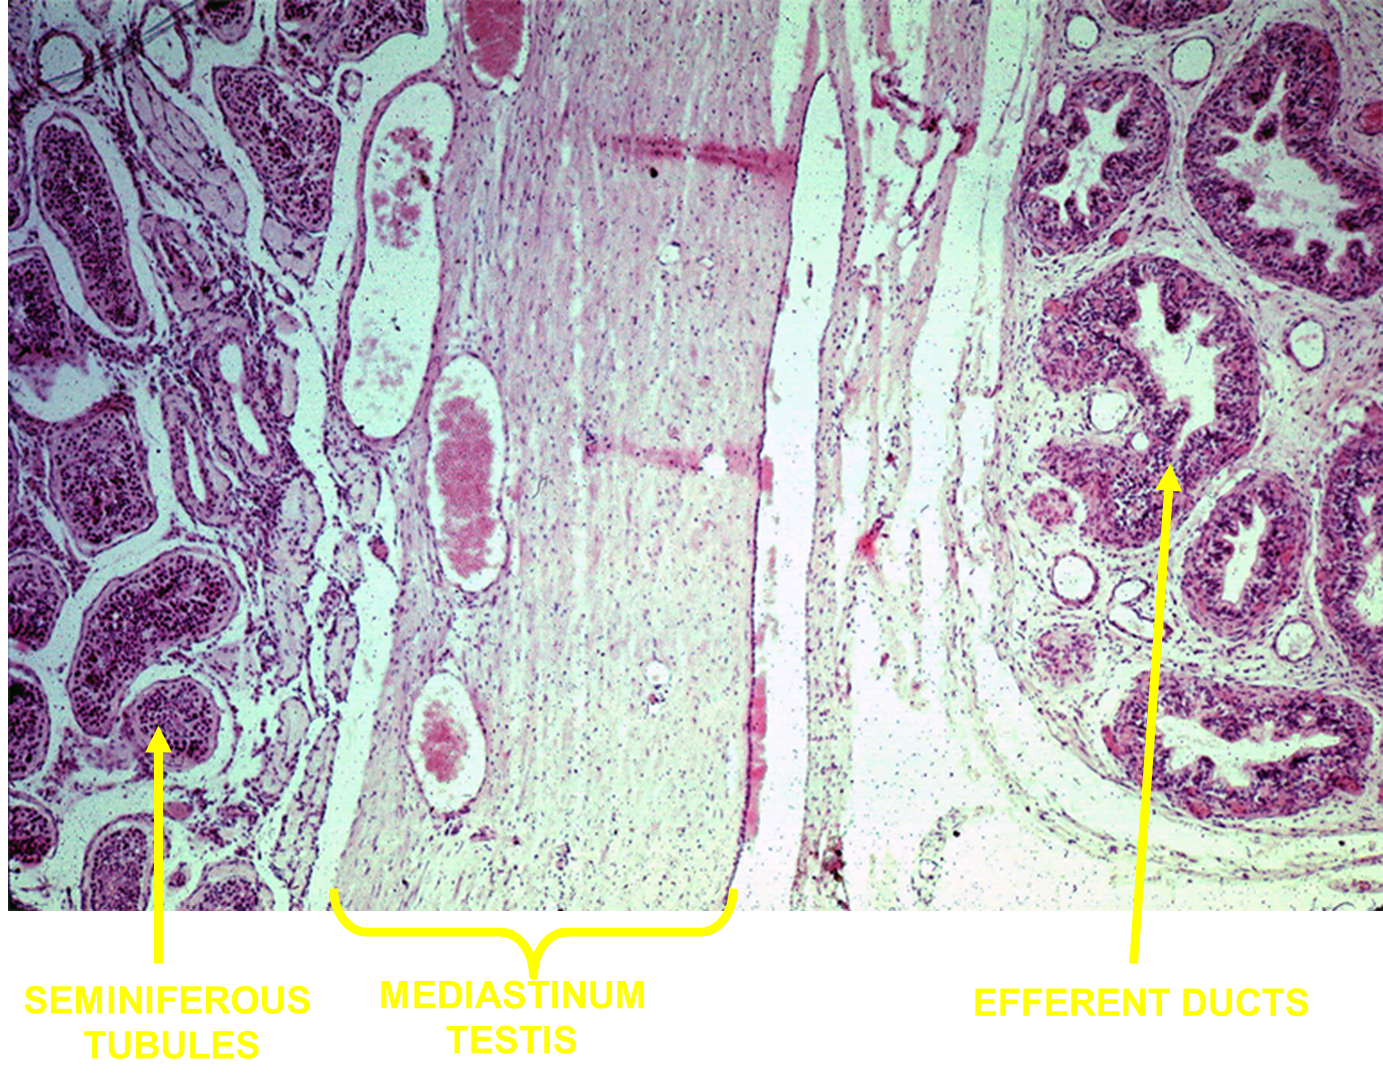

1) The testes are subdivided into lobules which are pyramid shaped areas

→ each lobule has around 1-4 to seminiferous tubules which are “blind end” or a dead-ended coiled tubule

2) sperm produced in the seminiferous tubules where it will exit to the rete testis

What are the Intratesticular Genital Ducts?

Tubuli Recti (straight tubules)

→ ducts leading out of the seminiferous tubules

Rete Testis

→ tubuli recti will empty together into the rete testis located in the mediastinum

→ formed from cuboidal cells

Efferent Ducts

→ the rete testis will deposit into the efferent ducts formed from ciliated tall columnar cells and cuboidal cells

Afterwards sperm enters into the epididymis